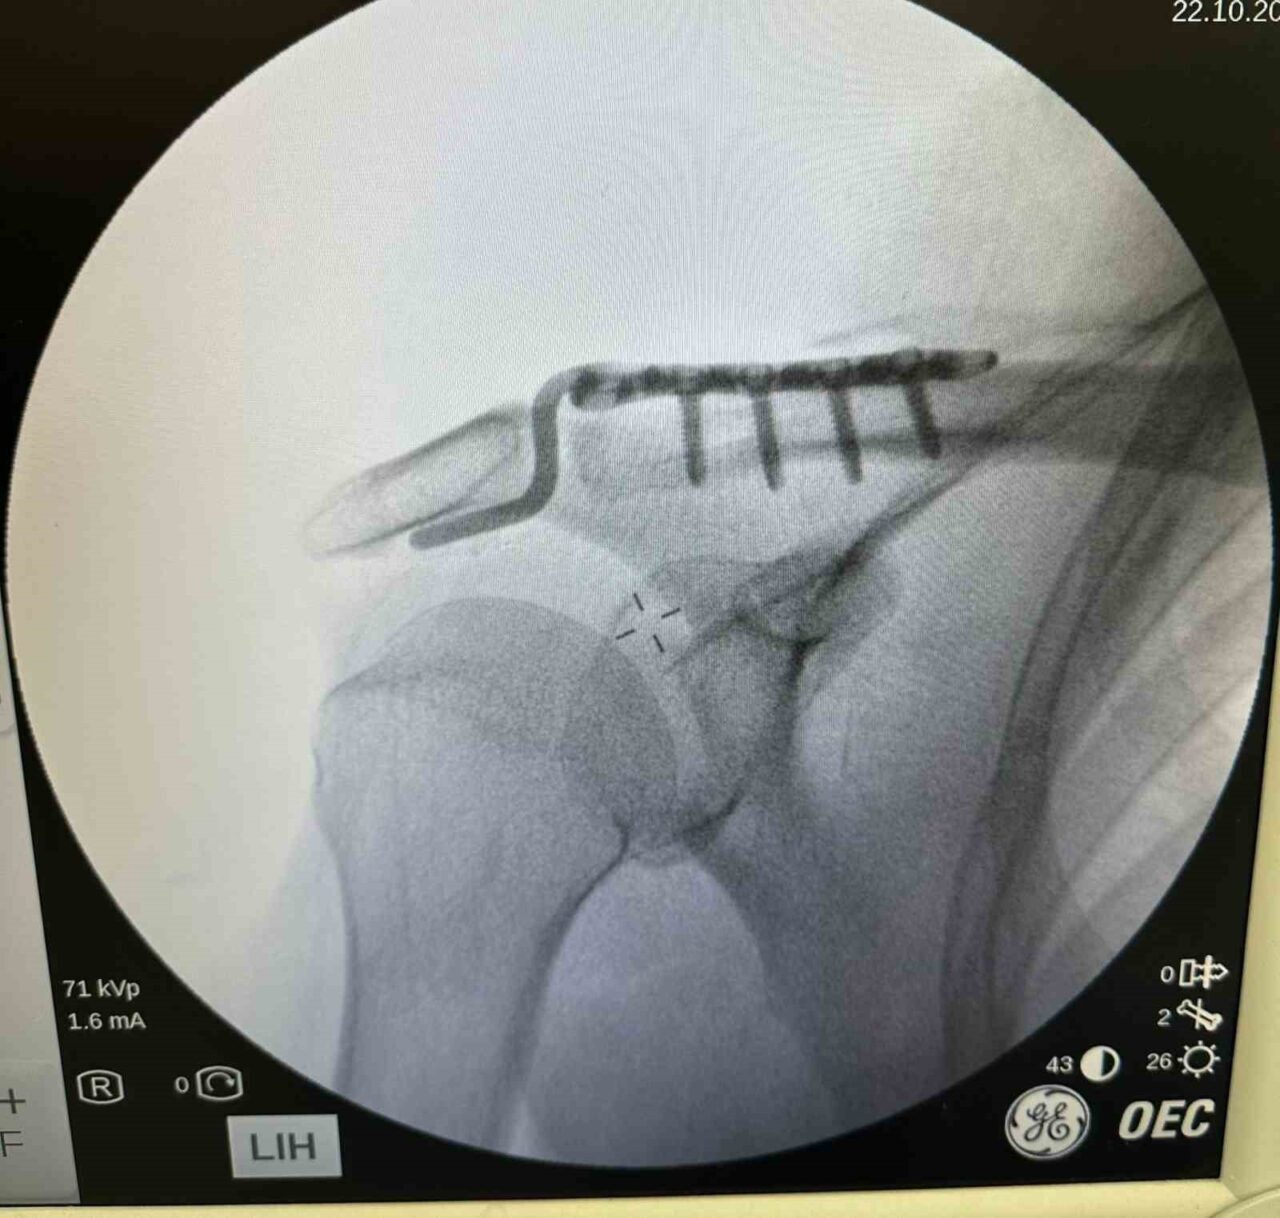

Olay, Mehmet Şerif Rençber’in tenis oynarken düştükten sonra omzunun çıkmasıyla meydana geldi. Rençber, tedavi için gittiği çeşitli sağlık kuruluşlarında yaşından dolayı ameliyat olamayacağını öğrendi. Ancak, Batman Eğitim ve Araştırma Hastanesi Ortopedi ve Travmatoloji Uzmanı Dr. Mehmet Yavuz Başer, özel bir plak kullanarak başarılı bir müdahale gerçekleştirdi.

Dr. Başer, durumuyla ilgili bilgi vererek, “Hastamız omuz çıkığı nedeniyle başvurdu. Çünkü tenis oynarken düşmesi sonucunda omzunda bir problemler oluştu. Genellikle bu tür yaralanmaları genç hastalarda görüyoruz. Ancak hastamız oldukça aktiftir. İlk değerlendirmede omuz eklemi yerinde değildi. Nadir kullanılan, hastanın kemik yapısına tam uyum sağlayan bir plak ile ameliyatı gerçekleştirdik,” ifadelerini kullandı.